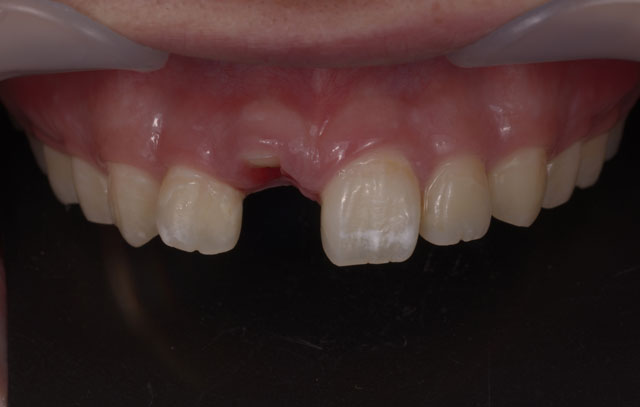

前歯のインプラント治療

前歯は周囲の骨が非常に薄いので抜歯後、時間の経過と共に歯茎は痩せて、骨も吸収して溶けてしまうことが多くあります

前歯のインプラント治療でとても重要なポイントは失った歯を回復してしっかり噛めるように機能を回復させることと、見た目が自然で人工物とわからないぐらいに綺麗にインプラント治療によって審美性を回復させることです。

しかし多くの場合、前歯の周囲の骨は非常に薄く、歯を失ったことになり顎の骨は吸収して痩せていき、それに伴って歯茎も下がってしまいます。

このままの状態でインプラント治療を行うと周りの歯と長さの違う不自然な被せ物(人工歯)になってしまい見栄えが悪く清掃性もよくありません。

そのため前歯のインプラント治療では、より正確な位置にインプラントを埋入することが求められ、インプラント周りの歯茎も自然な仕上がりになるようにインプラント周囲組織の骨や歯茎も回復をしてあげる必要があります。

コンピューターガイデッドインプラント治療 + 歯科用顕微鏡を用いたマイクロサージェリー 審美的に良好な結果が得られています

当院では、コンピューターガイデッド インプラント治療で正確な位置にインプラント手術を行い、そして前歯などの審美領域では顕微鏡を使用したマイクロサージェリー(顕微鏡下手術)を行うことで傷跡の目立ちにくい自然な仕上がりのインプラント治療を行っています。